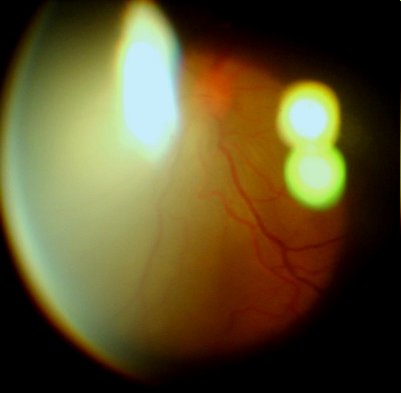

眼底:后极部视网膜渗出性脱离明显好转,后极部视网膜平伏,浅脱离,黄斑区仍然隆起。下方中周部仍可以见到隆起、皱褶脱离的视网膜。未见明显坏死灶。视网膜血管充盈扩张,右侧视乳头9点位可见线状出血

眼底像(前节照相机+90D,图像质量不高,见谅)

右眼可见视网膜隆起,血管充血扩张,9点位视盘上线状出血